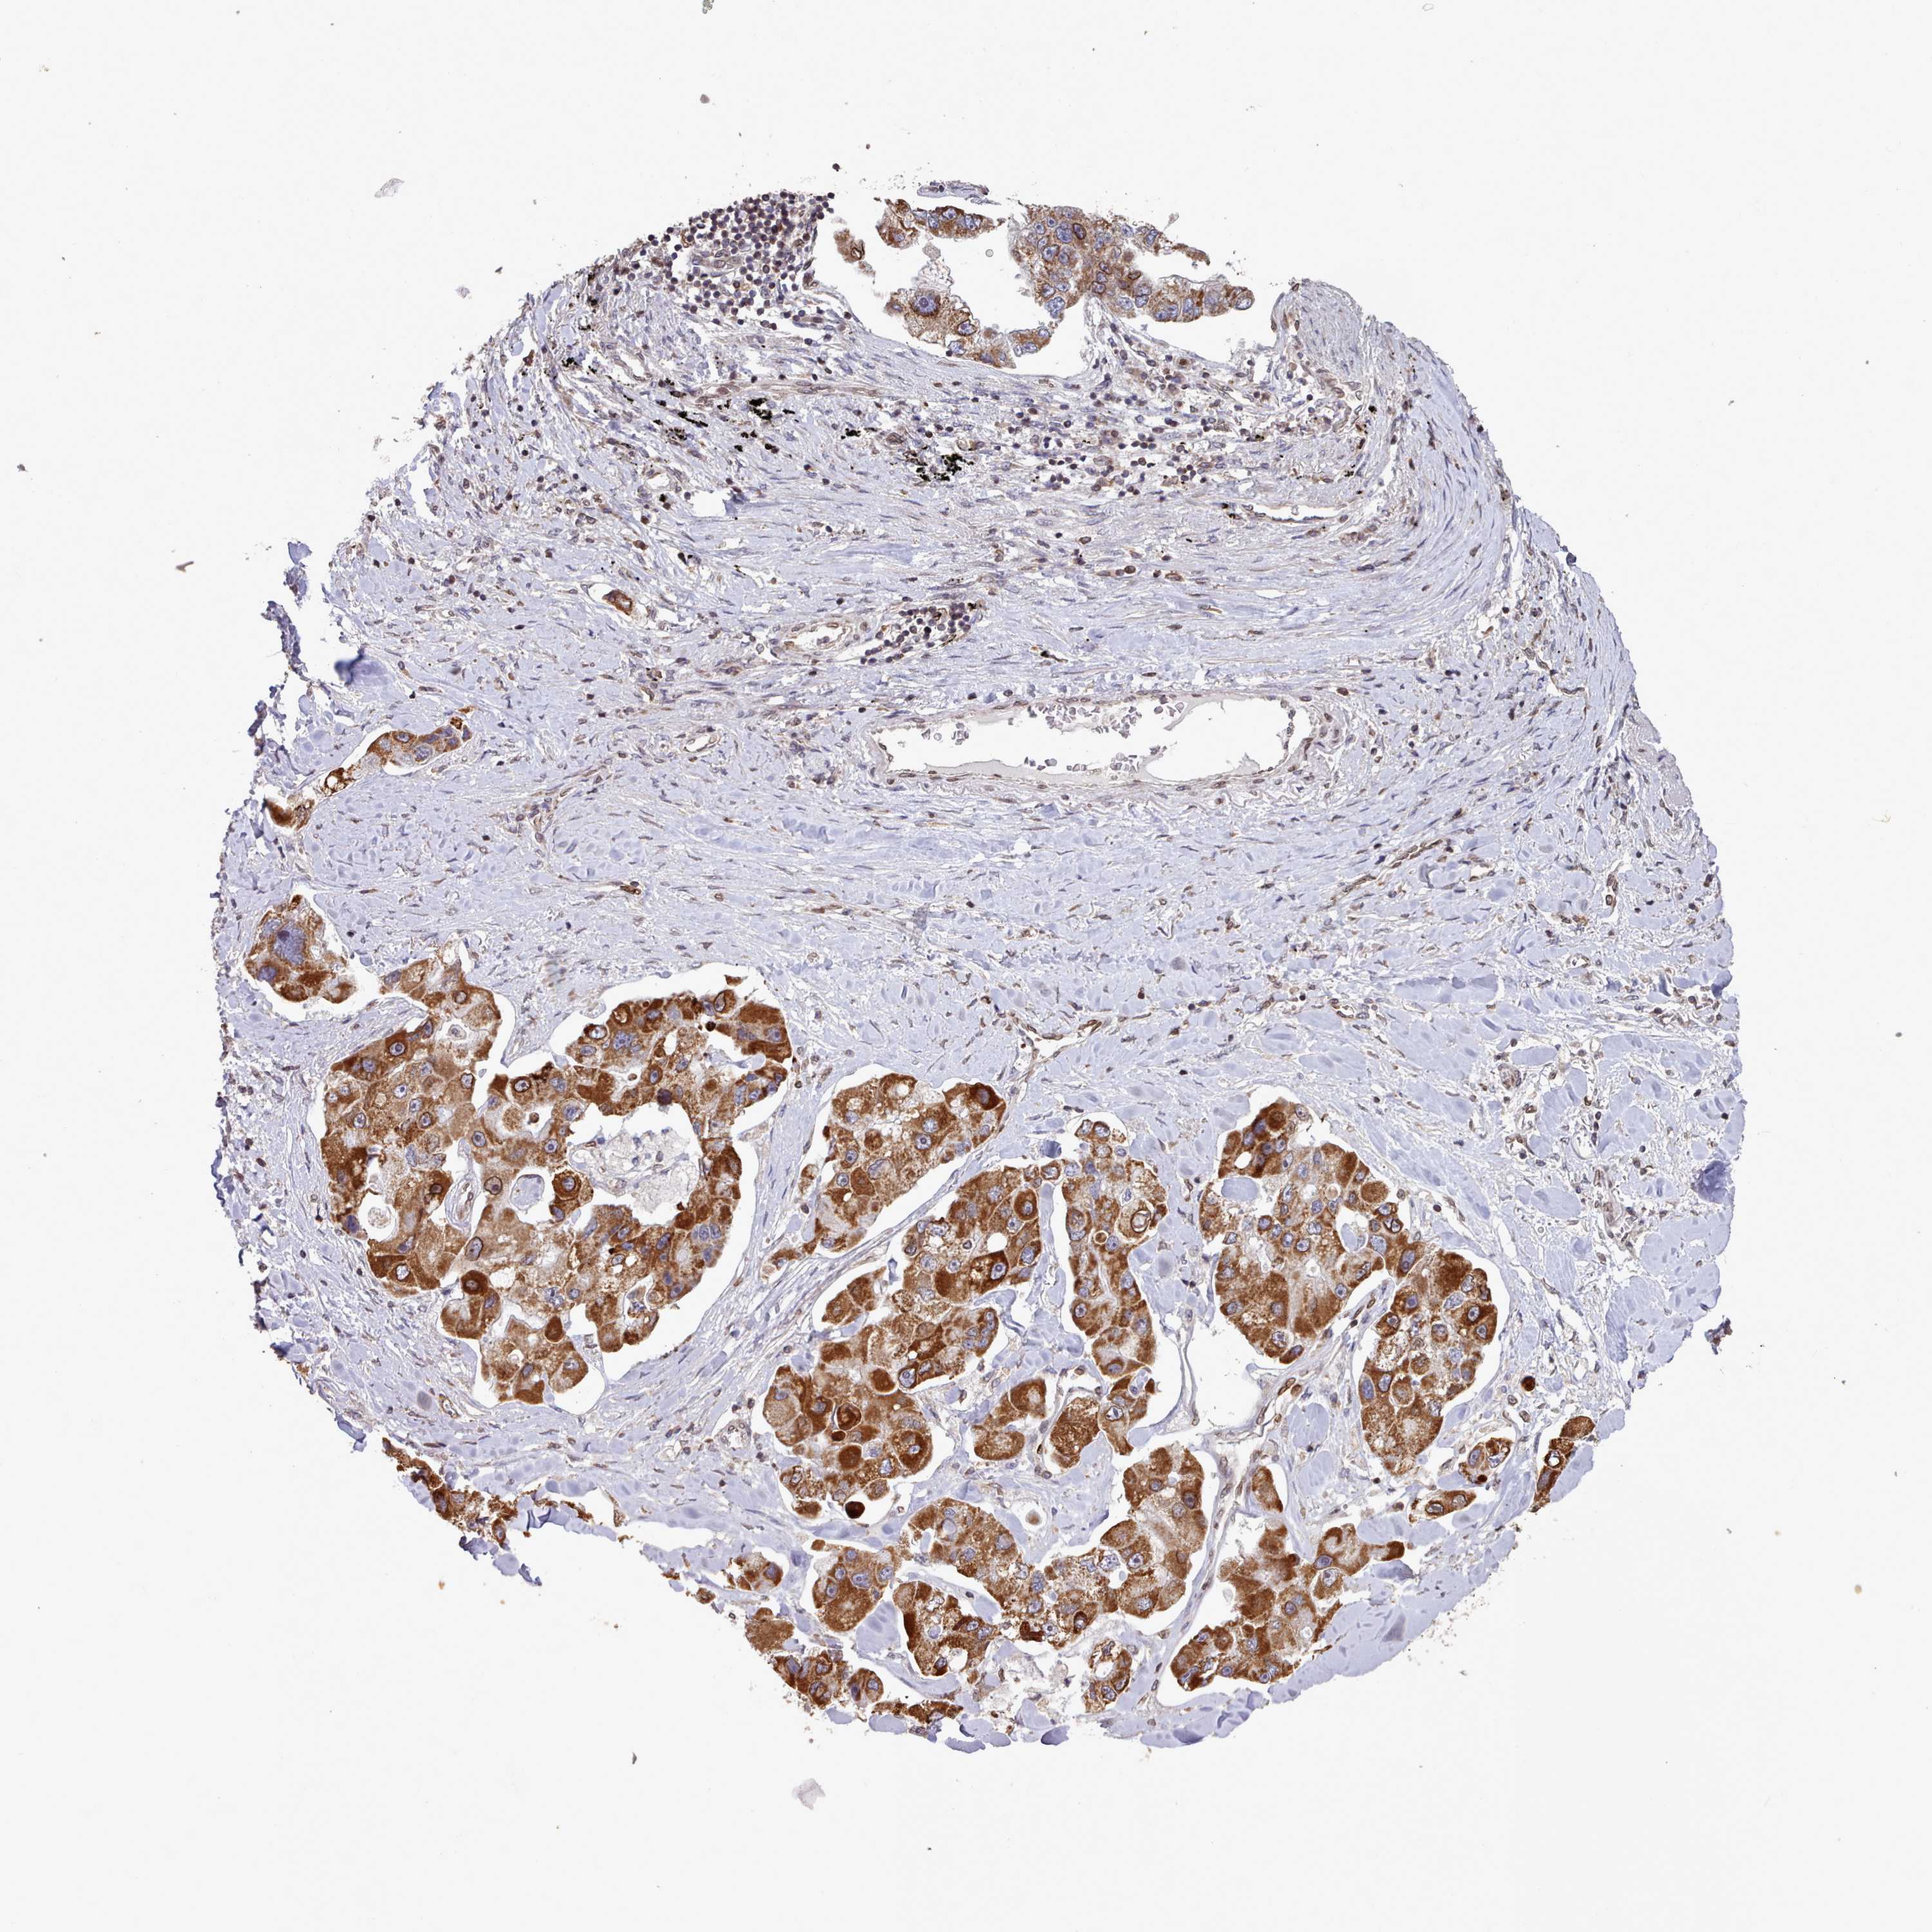

CANCER LUNG CANCER Show tissue menu

LUAD TCGA LUAD VALIDATION LUSC TCGA LUSC VALIDATION PROTEIN LUAD CPTAC PROTEIN LUSC CPTAC PROTEIN EXPRESSION

TOR1AIP1 is not prognostic in Lung Squamous Cell Carcinoma (TCGA)

TCGA RNA samplesi

Average pTPM 25.6

Number of samples 489